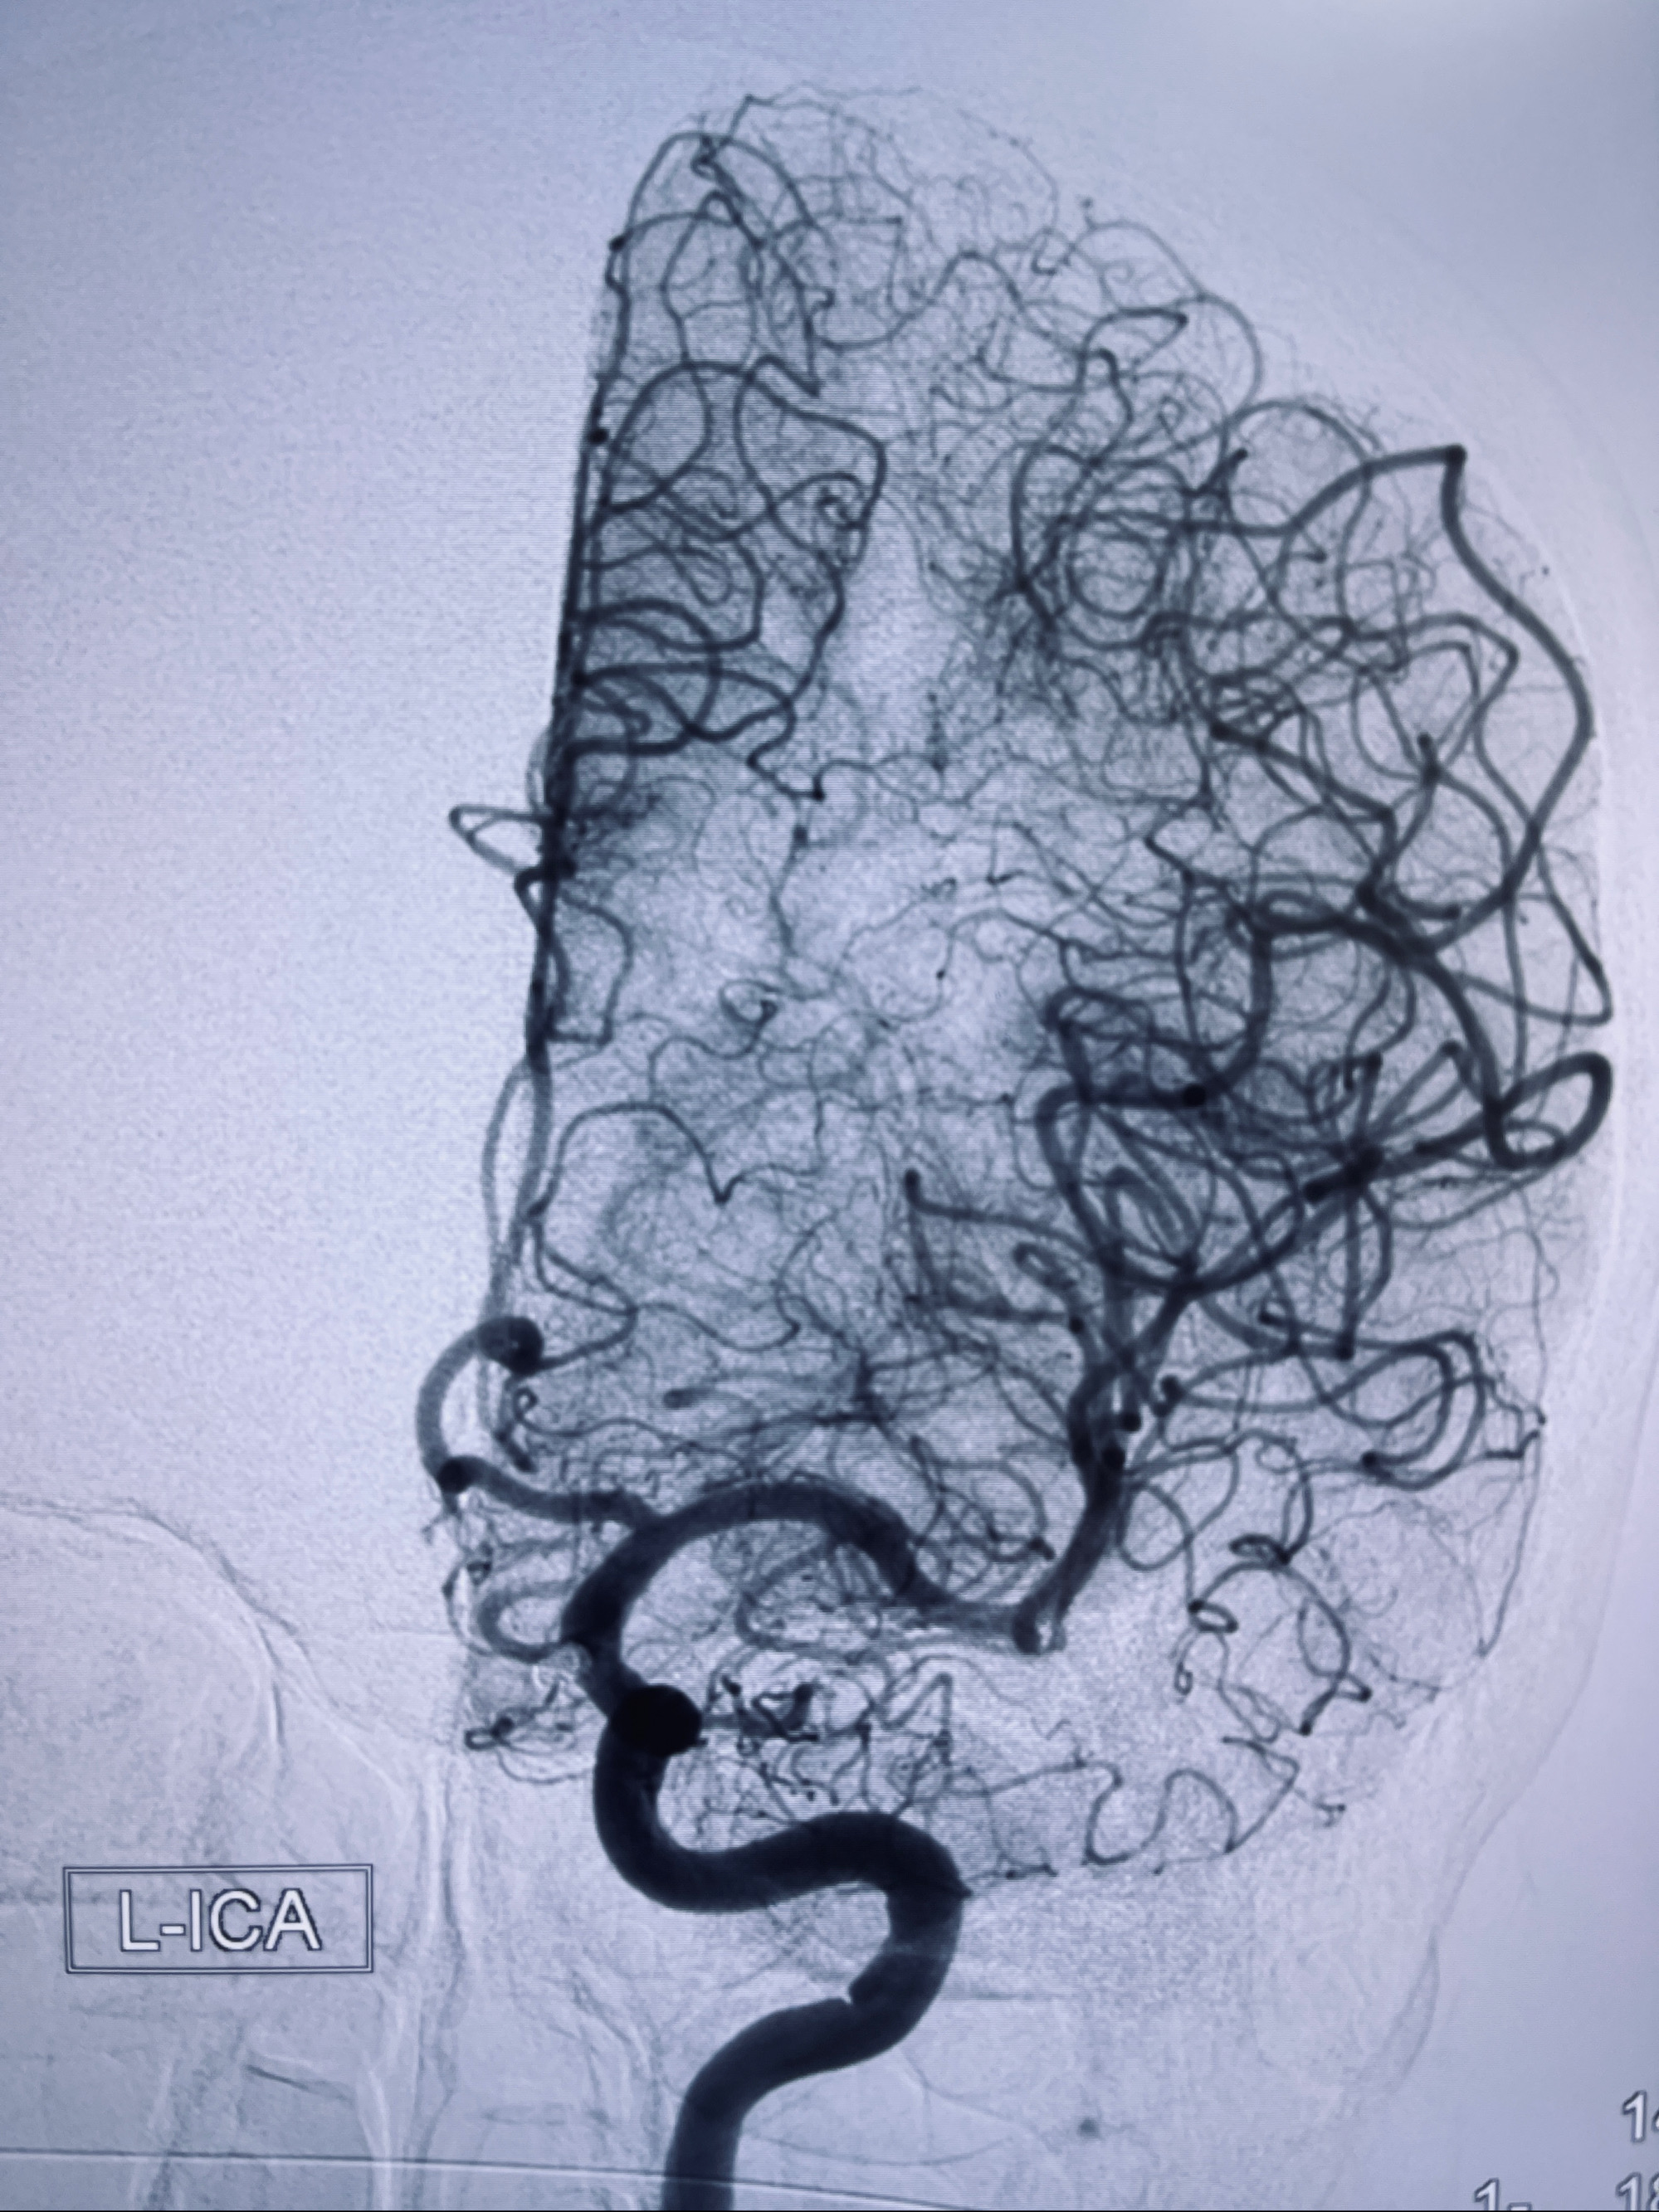

2022-09-29复查DSA

患者支架内血栓,给予阿司匹林+立普妥+依折麦布强化降脂干预